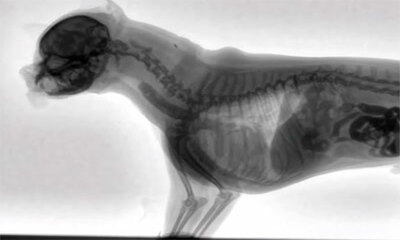

Un vétérinaire filme en fluoroscopie un chien qui mange

Vidéo assez particulière d’un chien filmé en fluoroscopie pendant qu'il mange. Pourquoi ? Car cela ce permet de voir la nourriture ingérer par l’animal se diriger jusqu'à l'estomac en temps réel. A savoir, la fluoroscopi...